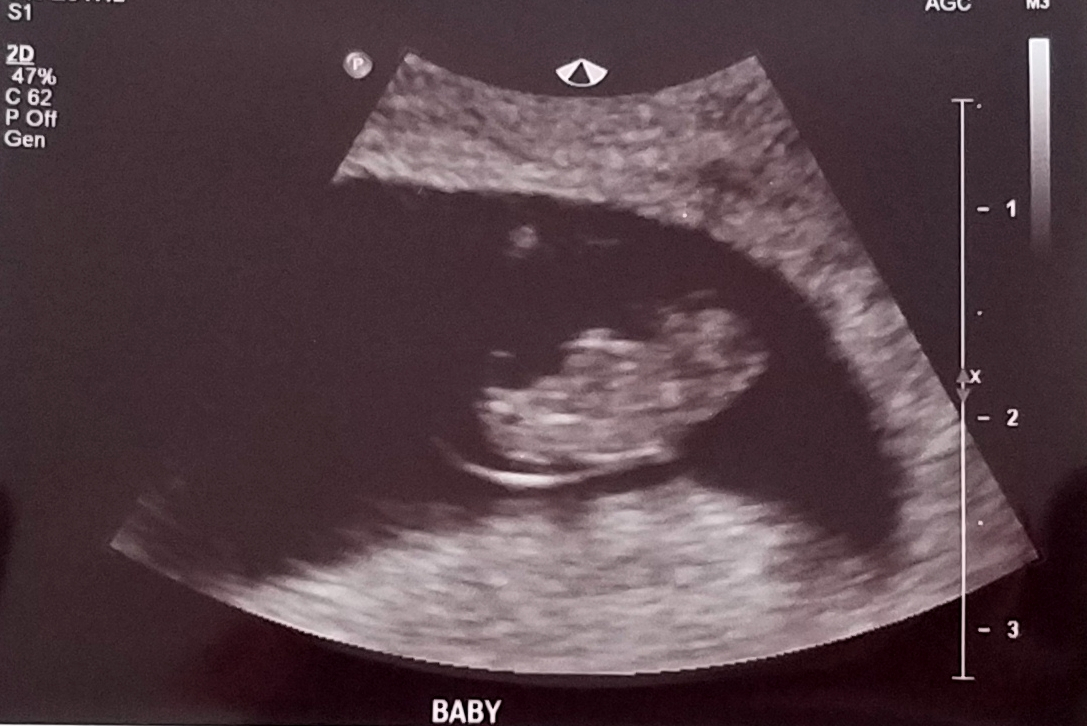

I had my first OB appointment today and got my first picture of my “bat” baby. I call him/her my bat baby because s/he is chillin’ upside down 🤪 HR was strong at 171. I just love this little bat baby already 🥰